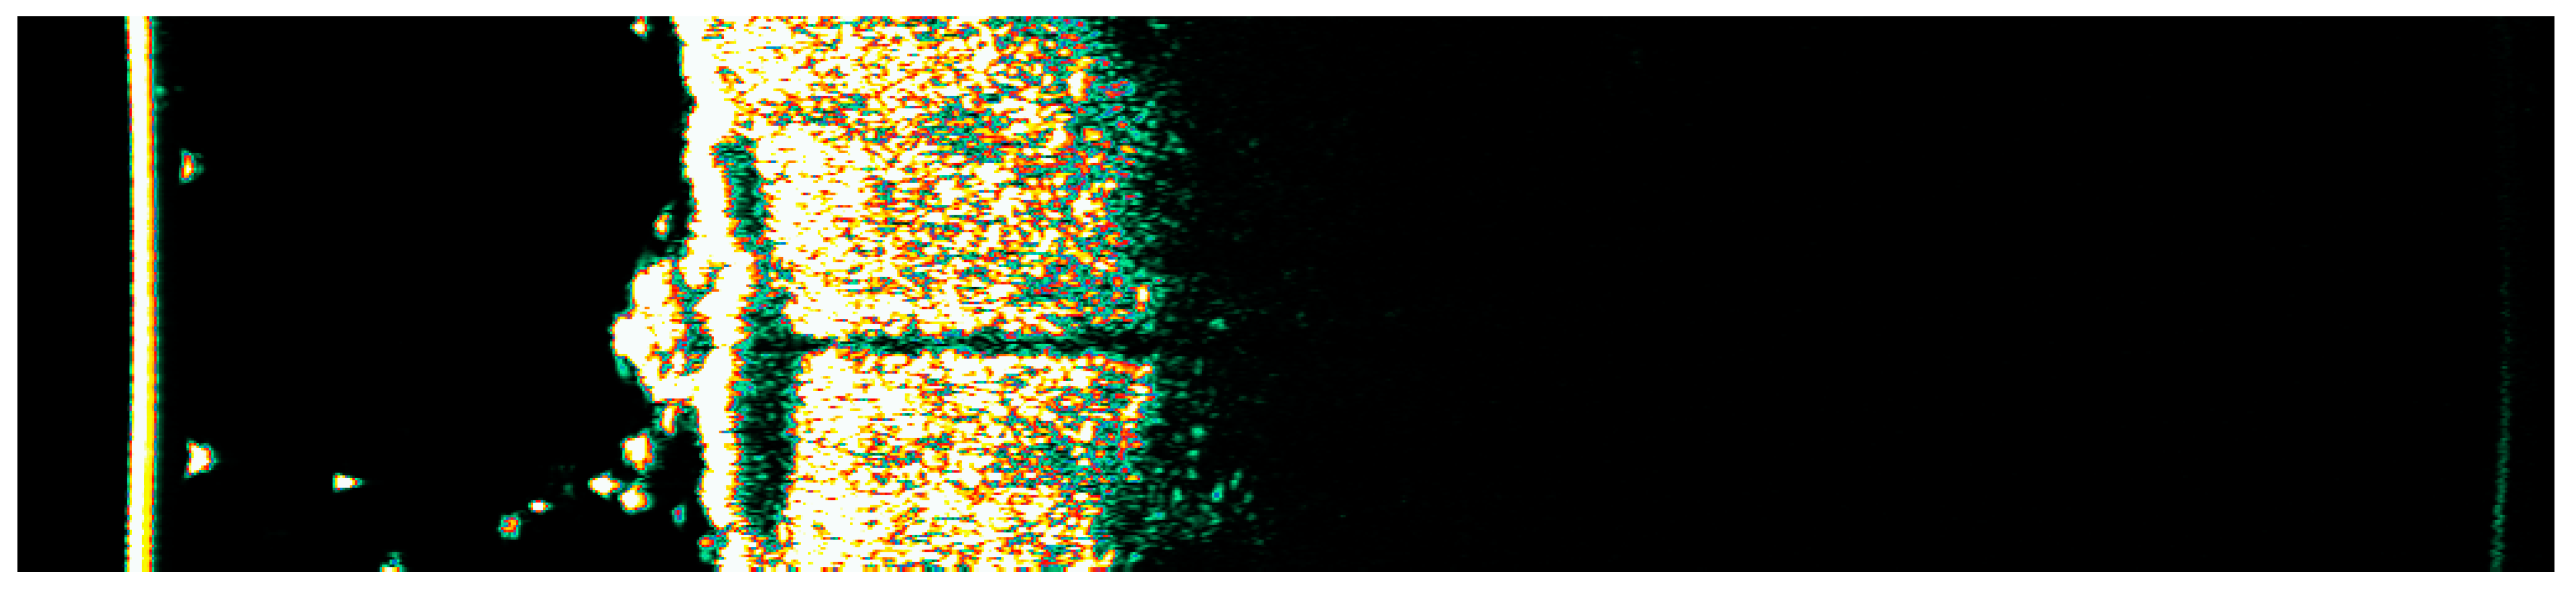

3.1. Clinical and Dermoscopic Involution of HIFU-Treated Basal Cell Carcinoma